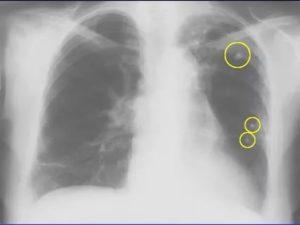

С помощью рентгеновского излучения и компьютерной обработки послойно анализируется внутреннее строение легких. Рентген легко проходит через ткани с низкой плотностью и задерживает там, где она высокая.

В отличии от рентгенографии, томография показывает орган во множестве сечений, тем самым увеличивается точность диагностики. Выявляются контуры, полости и глубина затемнений.

- Компьютерная томография легких (КТ) – высокоинформативный метод лучевой диагностики. С помощью компьютерного томографа производится ряд послойных снимков, позволяющих видеть состояние внутригрудных лимфоузлов, изменения в легочной и плевральной полостях, распространение опухолевого процесса, если таковой имеется. КТ назначают при обнаружении туберкулеза, пневмонии, рака. Во время процедуры пациент неподвижно лежит на специальной кушетке, раздевшись до пояса и сняв украшения. Кушетка помещается в томограф, чаще цилиндрический, но существуют и открытые модели данного аппарата. Снимки отображаются и сохраняются в компьютере. Их можно перенести и на цифровые носители. Процедура проведения компьютерной диагностики легких безвредна и безболезненна, специальной подготовки не требует, не показана беременным. Полное описание снимков и заключение обычно бывают готовы через несколько часов.